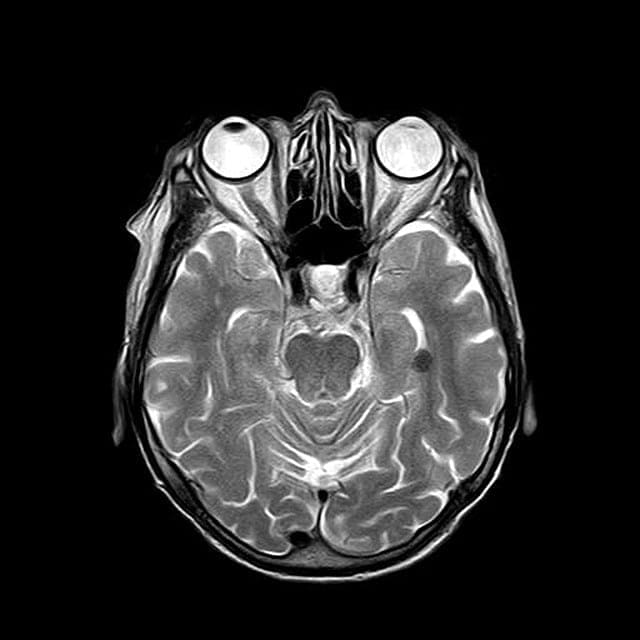

O modalitate de a masura raspunsul creierului la recompensa este de a examina activitatea in striatul ventral – zona cheie a sistemului nostru de recompensa responsabila de sentimentul de placere.

Studiul de fata si-a propus sa afle ce se intampla in striatul ventral la 21 de participanti cu tulburare bipolara si la 21 de participanti de control atunci cand apar schimbari momentane de dispozitie.

S-a folosit o tehnica numita imagistica prin rezonanta magnetica functionala (fMRI) pentru a masura fluxul de sange in creierul participantilor pentru a determina zonele active.

La toti participantii, s-a observat o activitate crescuta a creierului intr-o zona a acestuia care este implicata in experienta si constientizarea starilor de dispozitie tranzitorii – insula anterioara.

Cu toate acestea, se dovedeste ca in perioadele de impuls ascendent, in care participantii au castigat de multe ori, striatul ventral a aratat un semnal puternic, pozitiv numai la participantii cu tulburare bipolara.

De asemenea, s-a constatat ca nivelul de comunicare dintre striatul ventral si insula anterioara a fost redus la participantii cu tulburare bipolara.

In grupul de control, atat striatul ventral, cat si insula anterioara au inceput sa se uneasca.